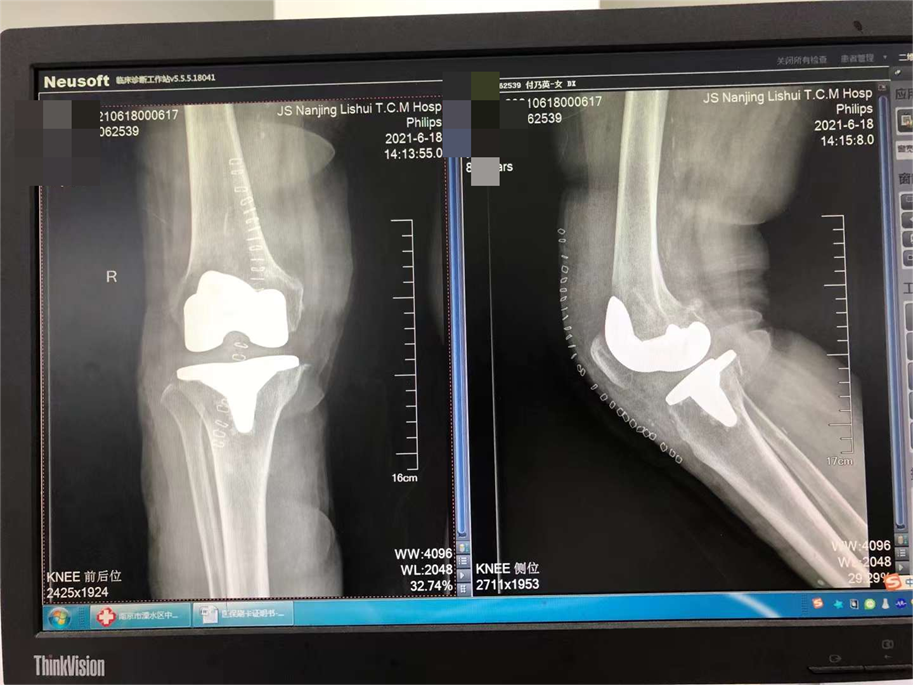

科室主任贾晋辉博士先后两次赴德国学习,在骨折微创手术,全髋关节置换,全膝关节置换,膝关节单髁置换、关节镜微创手术等方面引进当今最先进技术,已治愈了几千例患者,病人满意度很高。